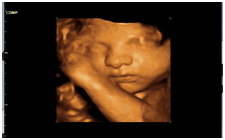

3D / 4D/ VOLUME ULTRASOUND – All applications

Photo